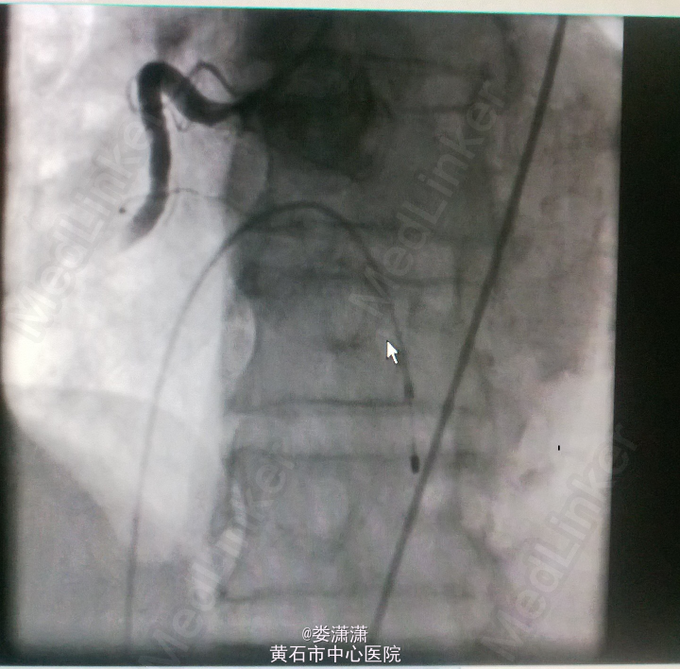

诊断:1.急性下壁心肌梗死(STEMI),心源性休克,心功能IV级(killip分级);2.高血压病2级(很高危);3.2型糖尿病;4.陈旧性脑梗塞;5.高尿酸血症。 处理——收入CCU后立即转去导管室行急诊冠脉造影术,术中见右冠中段以远全部闭塞,未见侧枝循环,前降支近中段见节段性狭窄70-80%,术中经6F Thrombuster血栓抽吸导管反复多次抽吸右冠,抽出数条红色血栓,并于右冠中段病变处植入Firebird 4.0*23mm药物支架,缝合鞘管时患者心电监护提示加速性实行逸博心律(110次/分左右),5min后突发室速、室颤,立即予床边电极除颤后转位室性逸博心律(105次/分)。返回病房后夜间患者多次出现室颤,予点击除颤、胺碘酮静滴等治疗后好转。术后24h内患者出现少尿,予静脉补液(5000ml/天左右)、利尿等,患者尿量基本维持在2000ml/天。术后辅查心电图见下壁导联ST段明显回落。余予抗血小板聚集、稳定斑块等治疗。